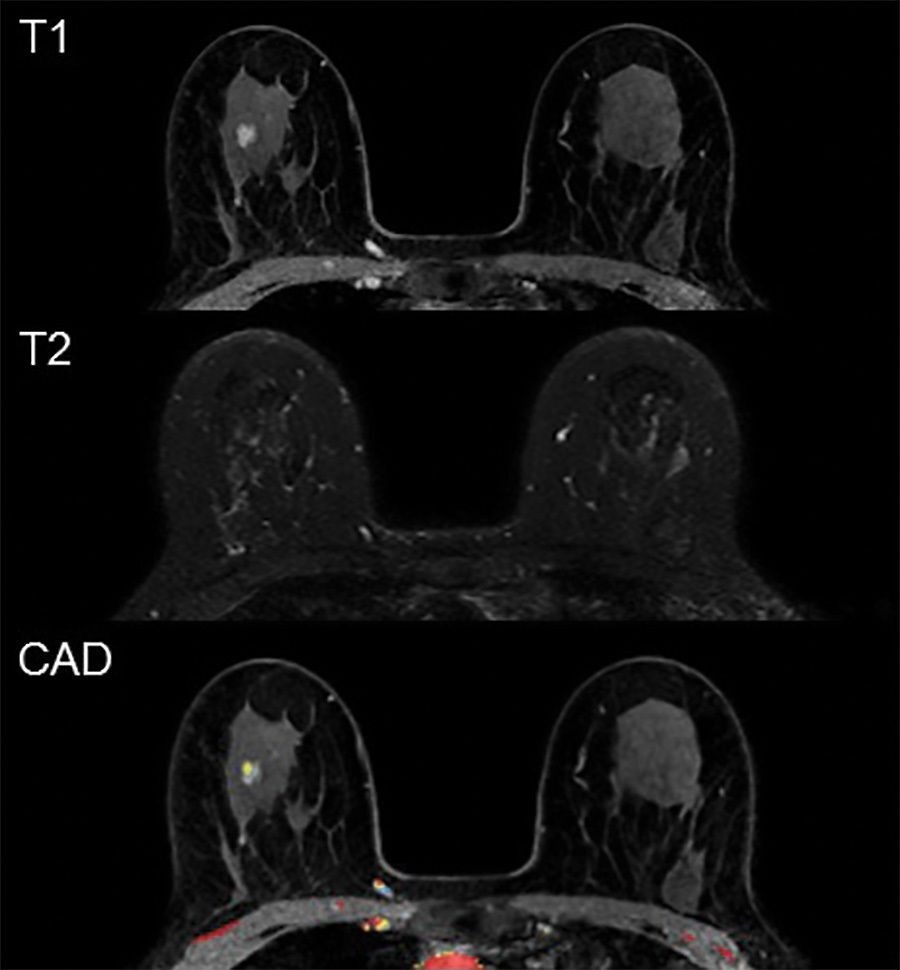

Un estudio identifica qué mujeres tienen el doble de riesgo de cáncer en ambas mamas

Las mujeres con cáncer en una mama pueden correr mayor riesgo de desarrollar cáncer en la mama opuesta si son portadoras de cambios genéticos específicos que las predisponen a desarrollar cáncer de mama, según ha demostrado un estudio dirigido por el Centro Oncológico Integral de Mayo Clinic (Estados Unidos).